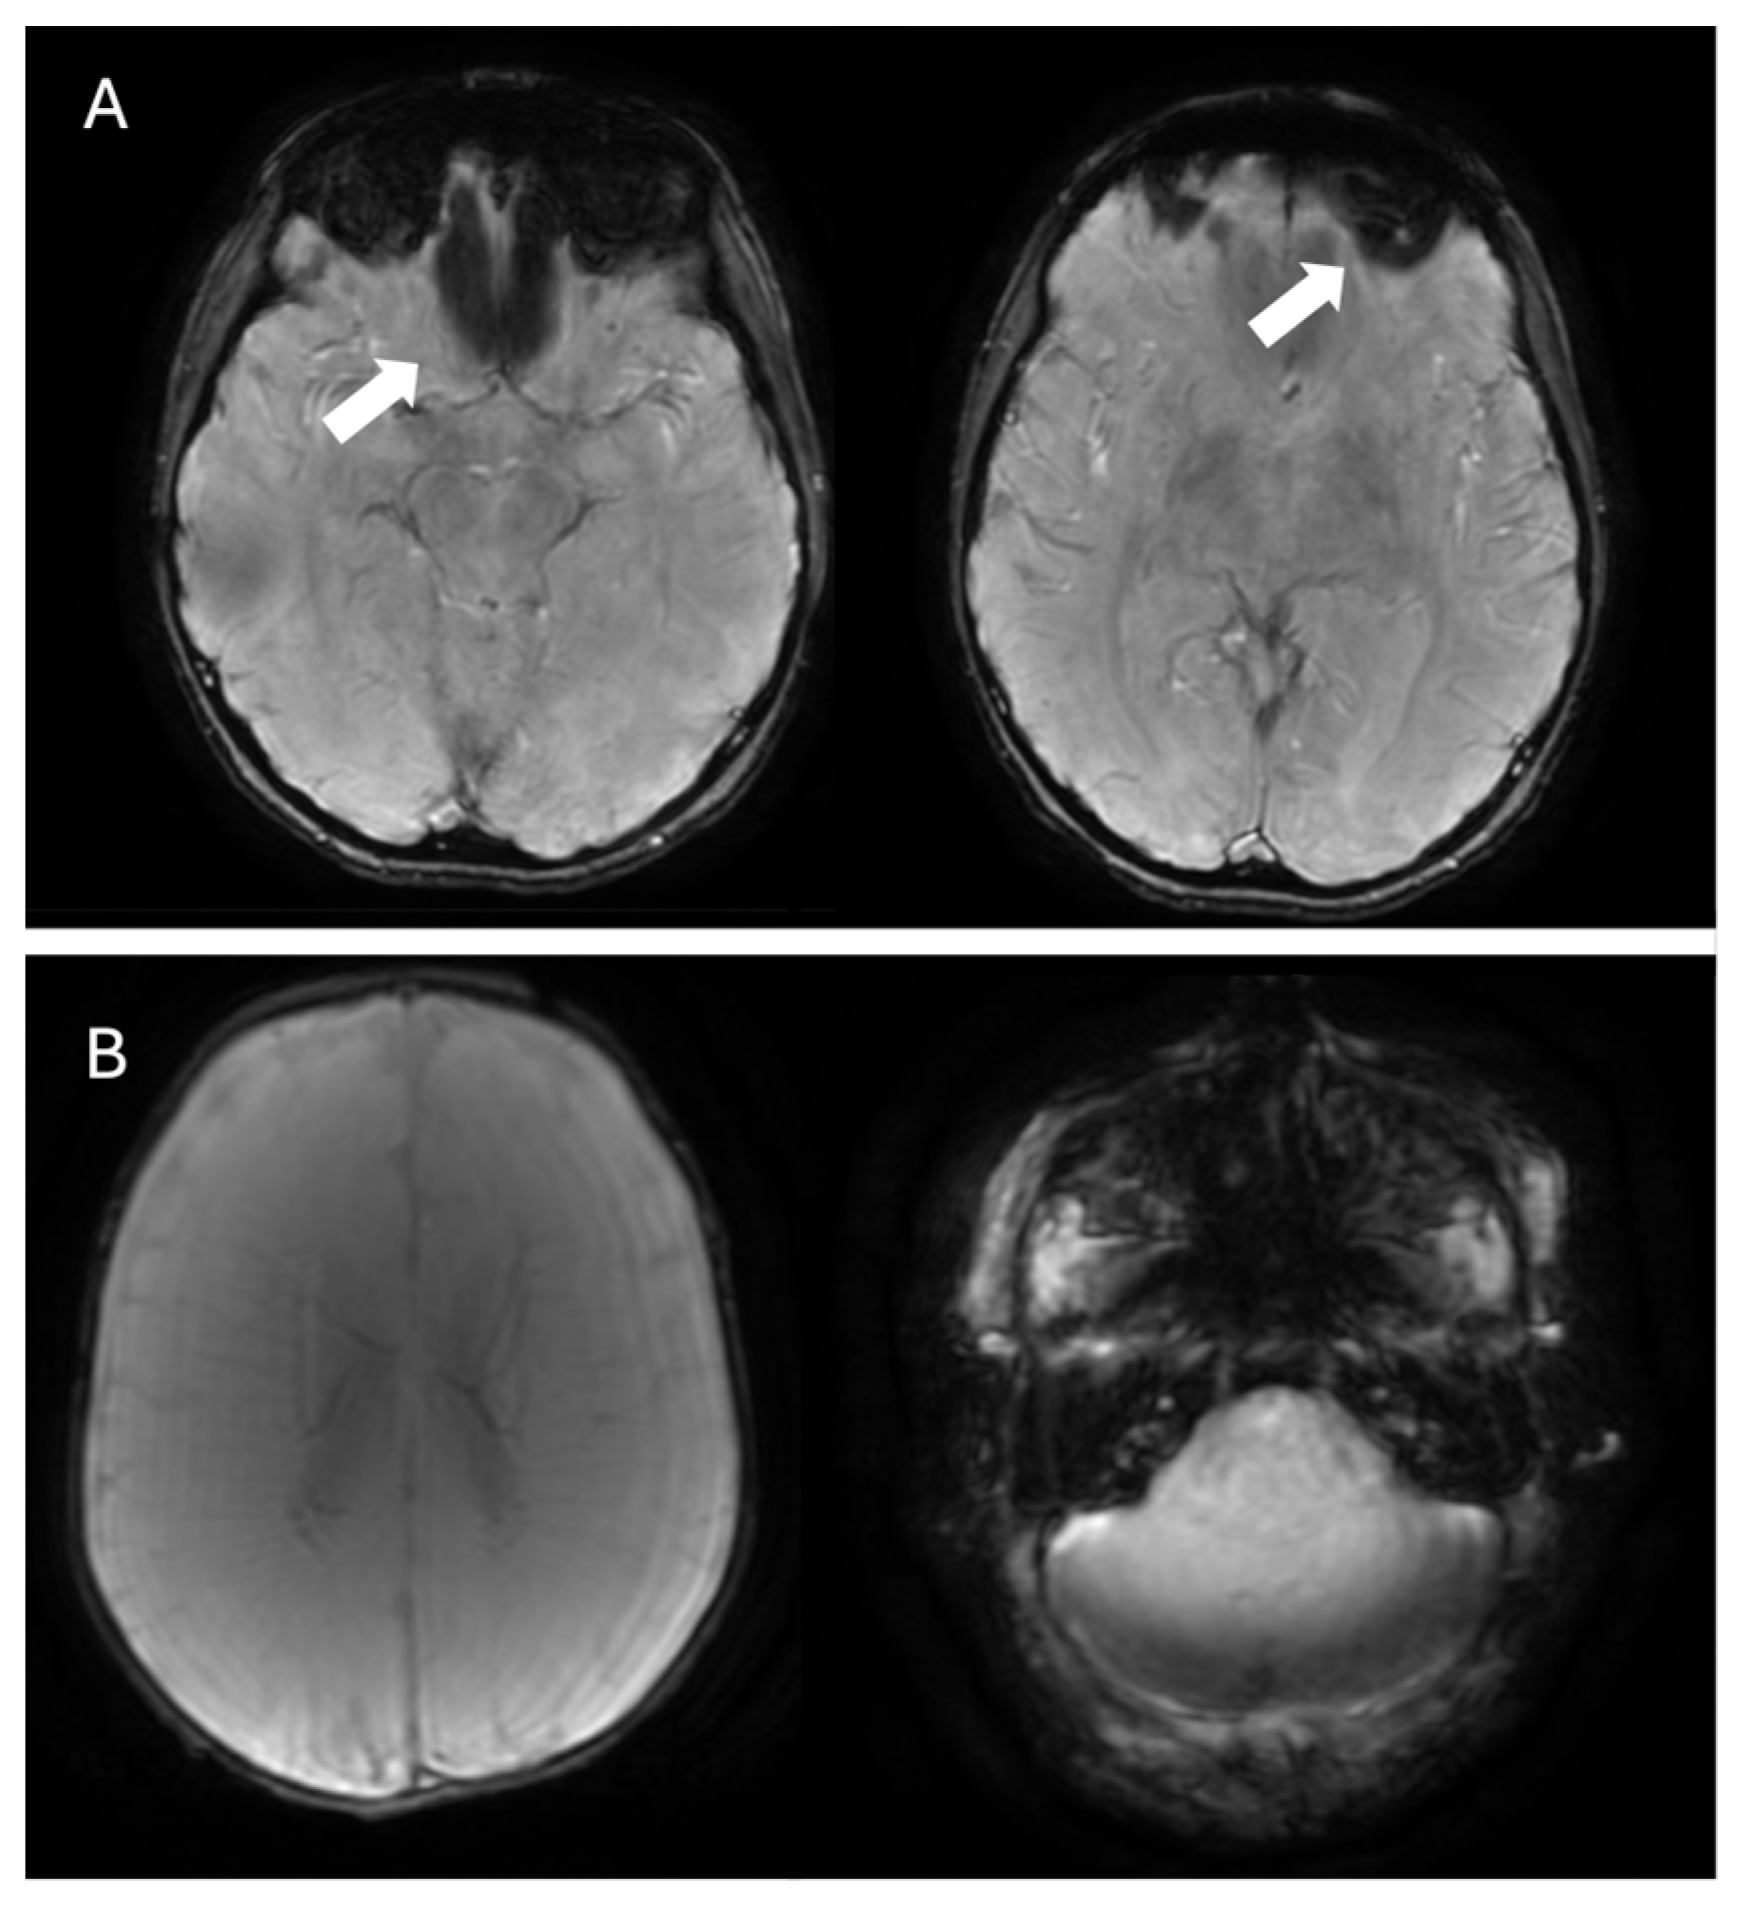

4.2. Multiple Sclerosis

| Cerebral amyloid angiopathy | Cortical or cortico–subcortical microbleeds | Small (2–10 mm), multiple (≥2), round or ovoid, and uniformly hypointense, primarily located in the frontal and parietal lobes (usually sparing the basal ganglia, assisting in the differential diagnosis with hypertensive microangiopathy) |

| Convexity subarachnoid hemorrhage/cortical superficial siderosis | Curvilinear regions of signal drop-out localized to one or more sulci | |